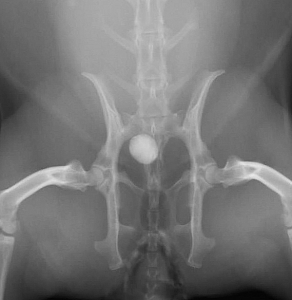

下の写真は膀胱結石が尿道結石となり尿路閉塞を生じた一連の変化をレントゲンで撮影したものです。数週間にわたる血尿と「排尿時のしぶり」と頻回尿を症状とする排尿障害を起こしていたウサギのものです。レントゲン検査では1cm程の膀胱結石が確認されました。

膀胱炎にやそれに伴う頻尿などの諸症状に対する対症療法を行ってもあまり症状の改善がみられないため、手術を計画しましたが、その前に排尿困難に陥って緊急で来院した際のレントゲン写真が下の二枚です。膀胱内にあった結石が尿道結石となり急性の尿路閉塞を生じています。